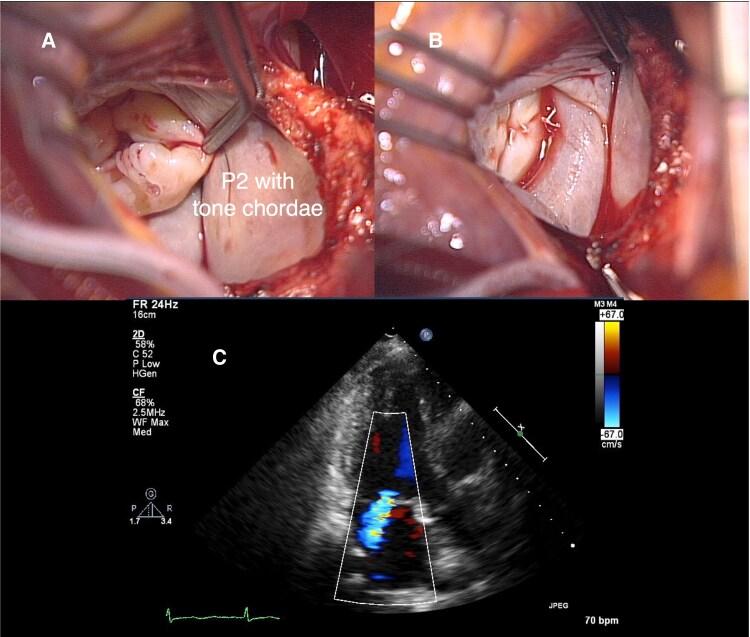

CASE SUMMARY

A 57-year-old woman with HS developed severe recurrent MR 4 years after initial surgical repair that intentionally omitted annuloplasty to minimize haemolysis risk. Given the risks of redo surgery and mechanical valve replacement, mitral valve transcatheter edge-to-edge repair (M-TEER) was performed. The procedure achieved successful MR reduction without causing haemolysis. At the 5-year follow-up, the patient maintained improved functional status with stable moderate MR and no evidence of haemolysis, despite her underlying condition.

DISCUSSION

This case demonstrates successful long-term outcomes of M-TEER for post-surgical recurrent MR in a patient with HS. The strategic approach-initial ring-less surgical repair followed by M-TEER-suggests a viable treatment pathway for patients with inherited haemolytic disorders, particularly when minimizing prosthetic material exposure is crucial.